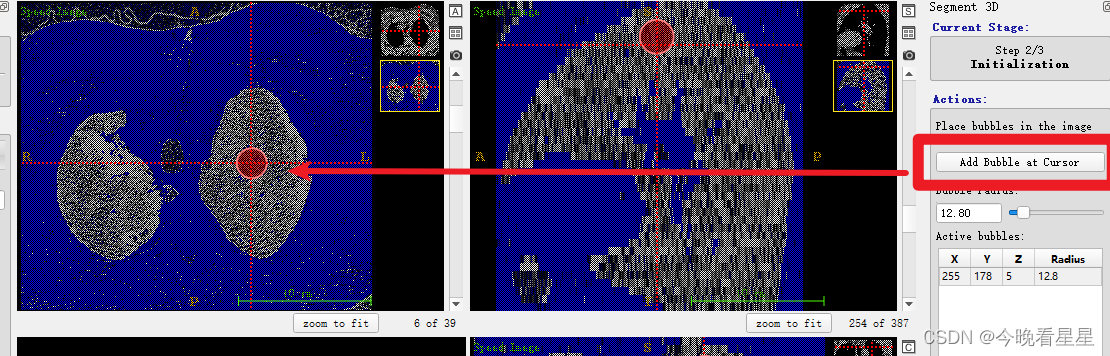

- 在要扩散的区域选择点,进行自动扩散

- 观察到区域在不断的扩散